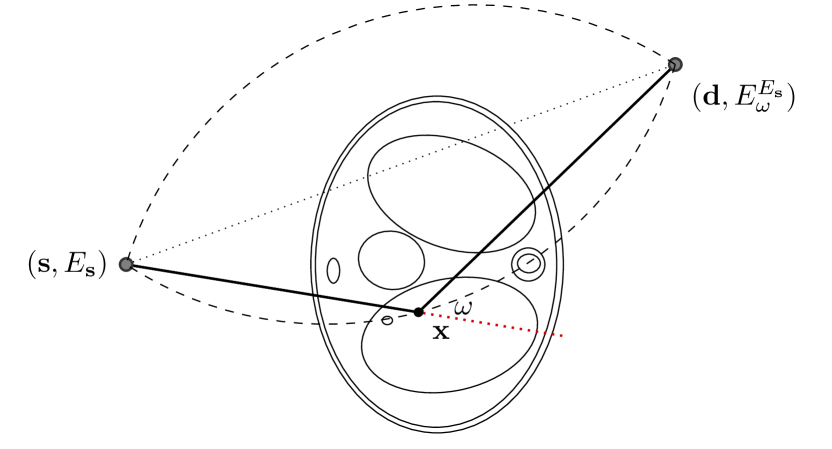

The Compton formula eq. 3 allows a representation of the scattering angle in terms of the energies. For fixed positions and and a measured energy , the set of possible scattering points are all for which (where is the angle between and ). Hence the locus of possible scattering events (dashed circular arcs in fig. 2) is characterized by

The TV penalty is defined by

We assume to measure a total of photons and compute synthetic data from eq. 11 for a phantom electron density modeling a transversal slice of a human thorax. The phantom (see fig. 2(b)) consists of characteristic functions of ellipses of different sizes and opacities and is a modified version of an earlier phantom which was used in [12]. It is 28.4 cm resp. 21.3 cm wide at its largest and smallest diameters and its gray values are chosen as electron densities of materials typical in a human thorax [15, 3, 30].

The main tool for the former step is a double application of the Compton formula eq. 3 which relates the two scattering angles and hence the two scattering points. Assume that a photon is emitted at the fixed point source with initial energy , scattered first at , then at and is finally measured at with energy (see fig. 4). Then the photon energy after the first scattering event is where is the first scattering angle. After the second scattering with angle , the remaining energy has to be . By rearranging, we obtain

With the first scattering parameters and the energy fixed, the second scattering point has to lie on the 2D cone opening at with angle , but also on the circular arcs connecting and with opening angle . The calculations amount to computing the intersection point of these sets, details are deferred to section 6. ∎

After the photon is scattered at , its trajectory is a straight line that forms an angle of with the incoming beam direction . Thus, its trajectory is part of the cone opening at with direction and aperture . As we only consider the two-dimensional case, the cone simplifies to two possible directions, resembling the shape of a ”V”, see the dotted lines in figure 4. We simplify notation by introducing a convention of a signed angle , restricting not to but to , although both yield the same energy after the first scatter event. The photon’s trajectory after the first scattering is then a subset of the line